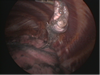

VATS